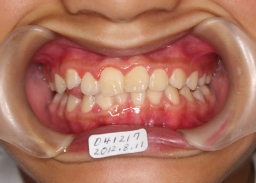

| 2011年12月17日(9才10ヶ月) 右側切歯(12番)が反対咬合 側切歯(12番)の反対咬合を改善するため、 12番が前方移動するようにワイヤーに 力を加えて接着剤でセット |

| 2012年02月05日(10才0ヶ月) 上記の約2ヵ月後 12番の反対咬合が改善 現在小臼歯や犬歯が生えるのを待っています。 |